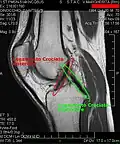

MRI

Both anterior cruciate ligament (ACL) and posterior cruciate ligaments (PCL) are hypointense on both T1 and T2 weighted images of MRI. However, some high signal striations are often seen at the distal part of the ACL, making ACL higher intensity than PCL on MRI scans.[20]

The knee is stabilized by a pair of cruciate ligaments. These ligaments are both extrasynovial, intracapsular ligaments.[20] The anterior cruciate ligament (ACL) stretches from the lateral condyle of femur to the anterior intercondylar area.[13] The ACL prevents the tibia from being pushed too far anterior relative to the femur.[13] It is often torn during twisting or bending of the knee.[21] The posterior cruciate ligament (PCL) stretches from medial condyle of femur to the posterior intercondylar area. This ligament prevents posterior displacement of the tibia relative to the femur.[13] Injury to this ligament is uncommon but can occur as a direct result of forced trauma to the ligament.